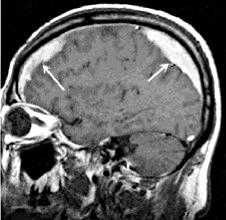

На фото субарахноидальное кровоизлияние на КТ

Диагноз выставляется на основании данных КТ, которая позволяет не только выявить кровоизлияние, но и получить данные о состоянии ликворной системы, распространенности процесса, наличии отека мозга.

МРТ реже применяется при ранней диагностике, но является более чувствительным методом для диагностики патологии спустя несколько дней.